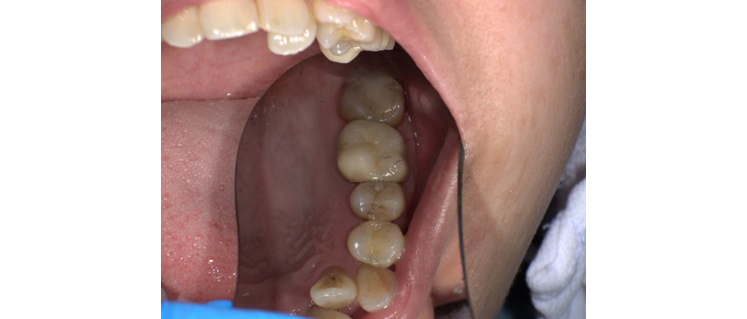

【症例No.3】左下奥歯 セラミックインレー修復/30代女性

Before

After

セラミックインレーは自然な色味とフィット感に優れ、隣の歯との調和も抜群です。治療後は見た目の違和感がなく、機能面でも問題なく使用いただけています。